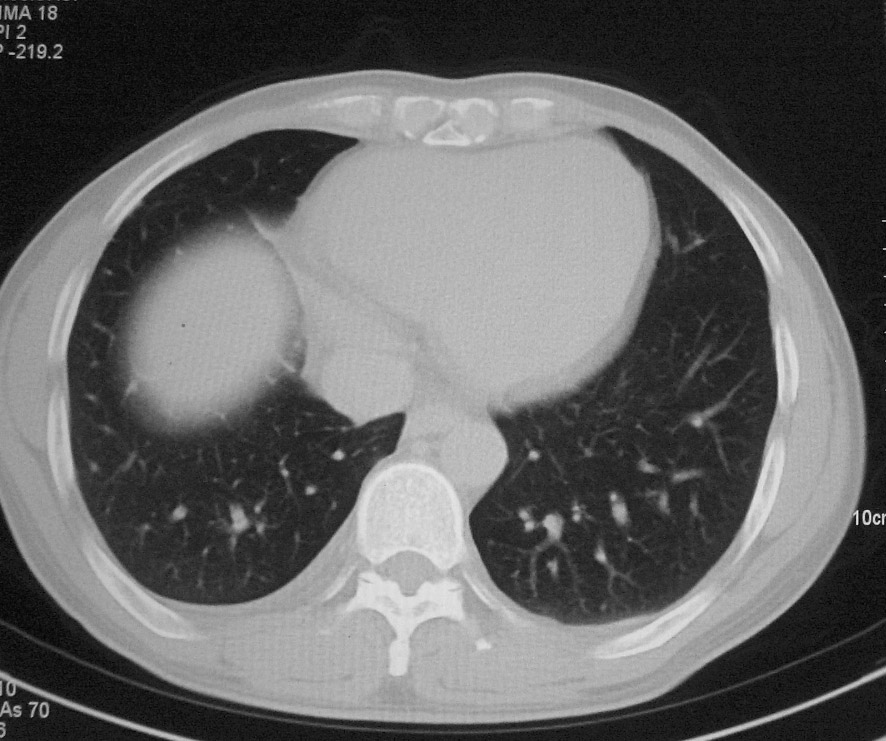

标题: CT5485:[原创]肺部占位请讨论

右肺上叶中央型肺癌并上叶肺不张、纵隔淋巴结肿大

右上叶支气管肺癌并右上叶阻塞性不张,右侧少量胸腔积液.

右上肺中央性肺癌伴右侧胸腔少量积液!右上肺胸膜下还有一小病灶,不完全排除结核,但个人支持恶性肿瘤!建议早穿刺活检。

右肺上叶中央型肺癌并上叶肺不张、纵隔淋巴结肿大.右侧少量胸腔积液。

右上肺中心型肺癌并肺不张,纵膈淋巴结肿大。右侧少量胸腔积液。

右肺上叶不张,考虑中央型肺癌。右侧胸膜肥厚

右肺上叶中央型肺癌并阻塞性炎症、阻塞性肺不张……